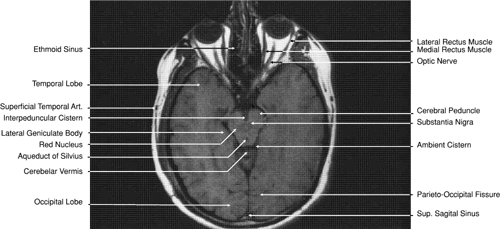

Fig. 32. A. Axial computed tomography soft tissue image at the level of suprasellar cistern. B. Axial computed tomography soft tissue image at the level of thalamus. C. Axial T1-weighted image at the level of thalamus.

The globe is shown in Figure 12. The orbit and periorbital structures are shown in Figures 13 through 16, and the optic canal is shown in Figures 17 through 26. The cavernous sinus and optic chiasm are shown in Figures 27 and 28, and the posterior visual pathway and cranial nerves are shown in Figures 29 through 33.